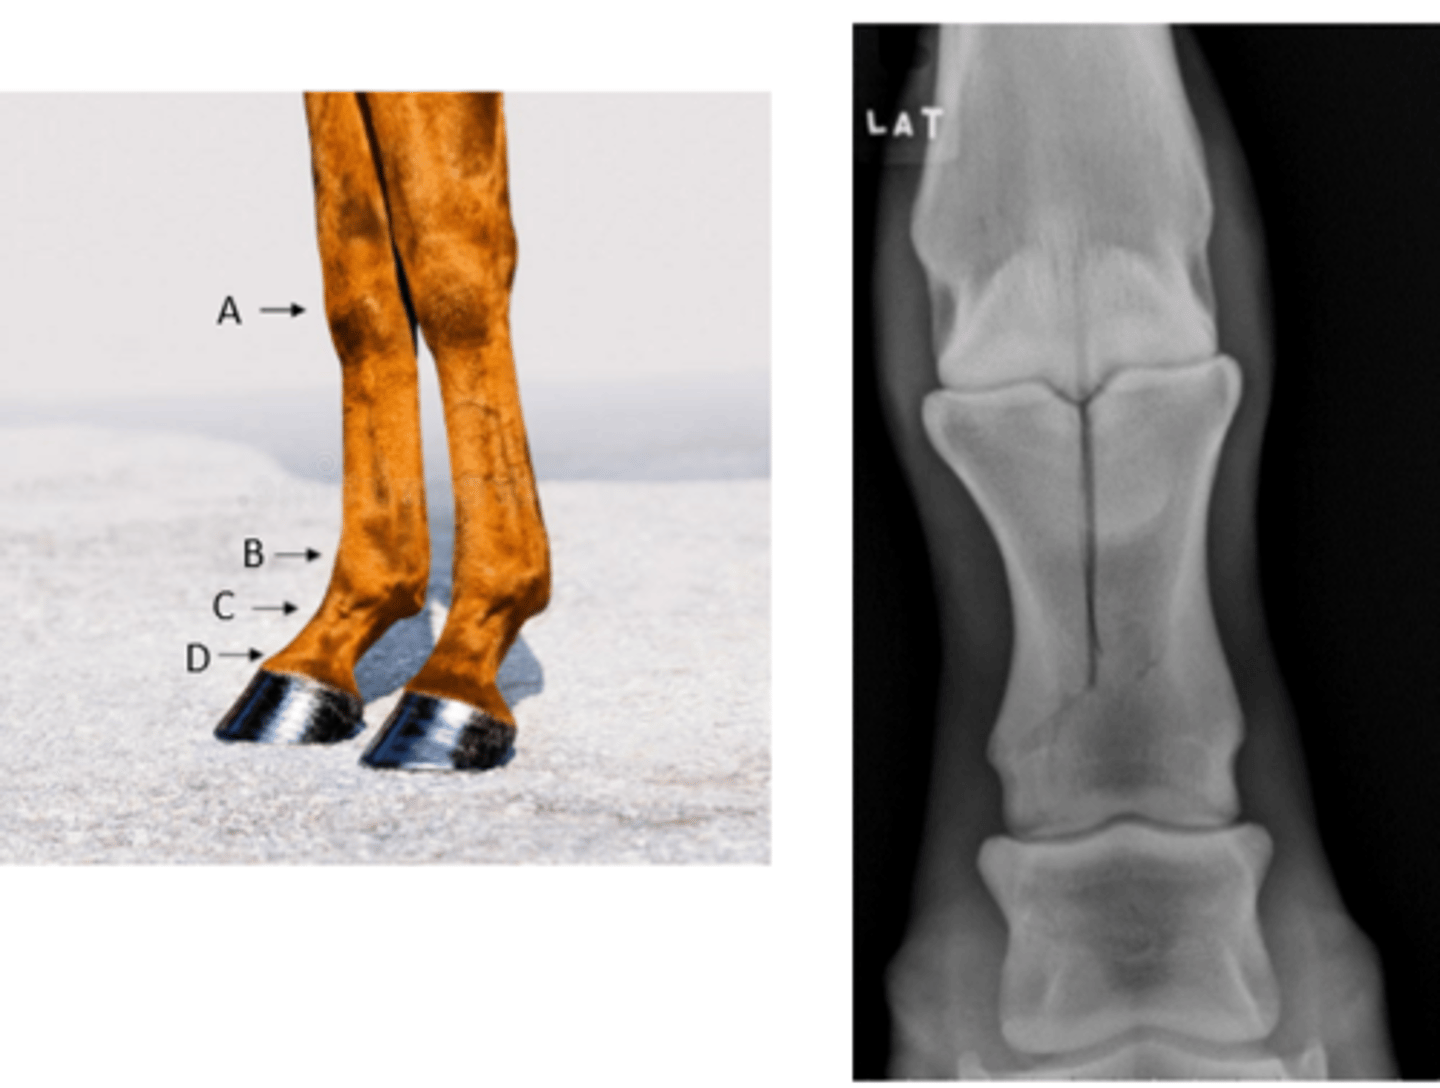

Enlarged dorsal aspect of the pastern

An owner sends a picture of this horse's leg. Describe the abnormality.

High ringbone

What is the layman's term for this lesion?

Arthodesis

What is the preferred treatment for this problem?